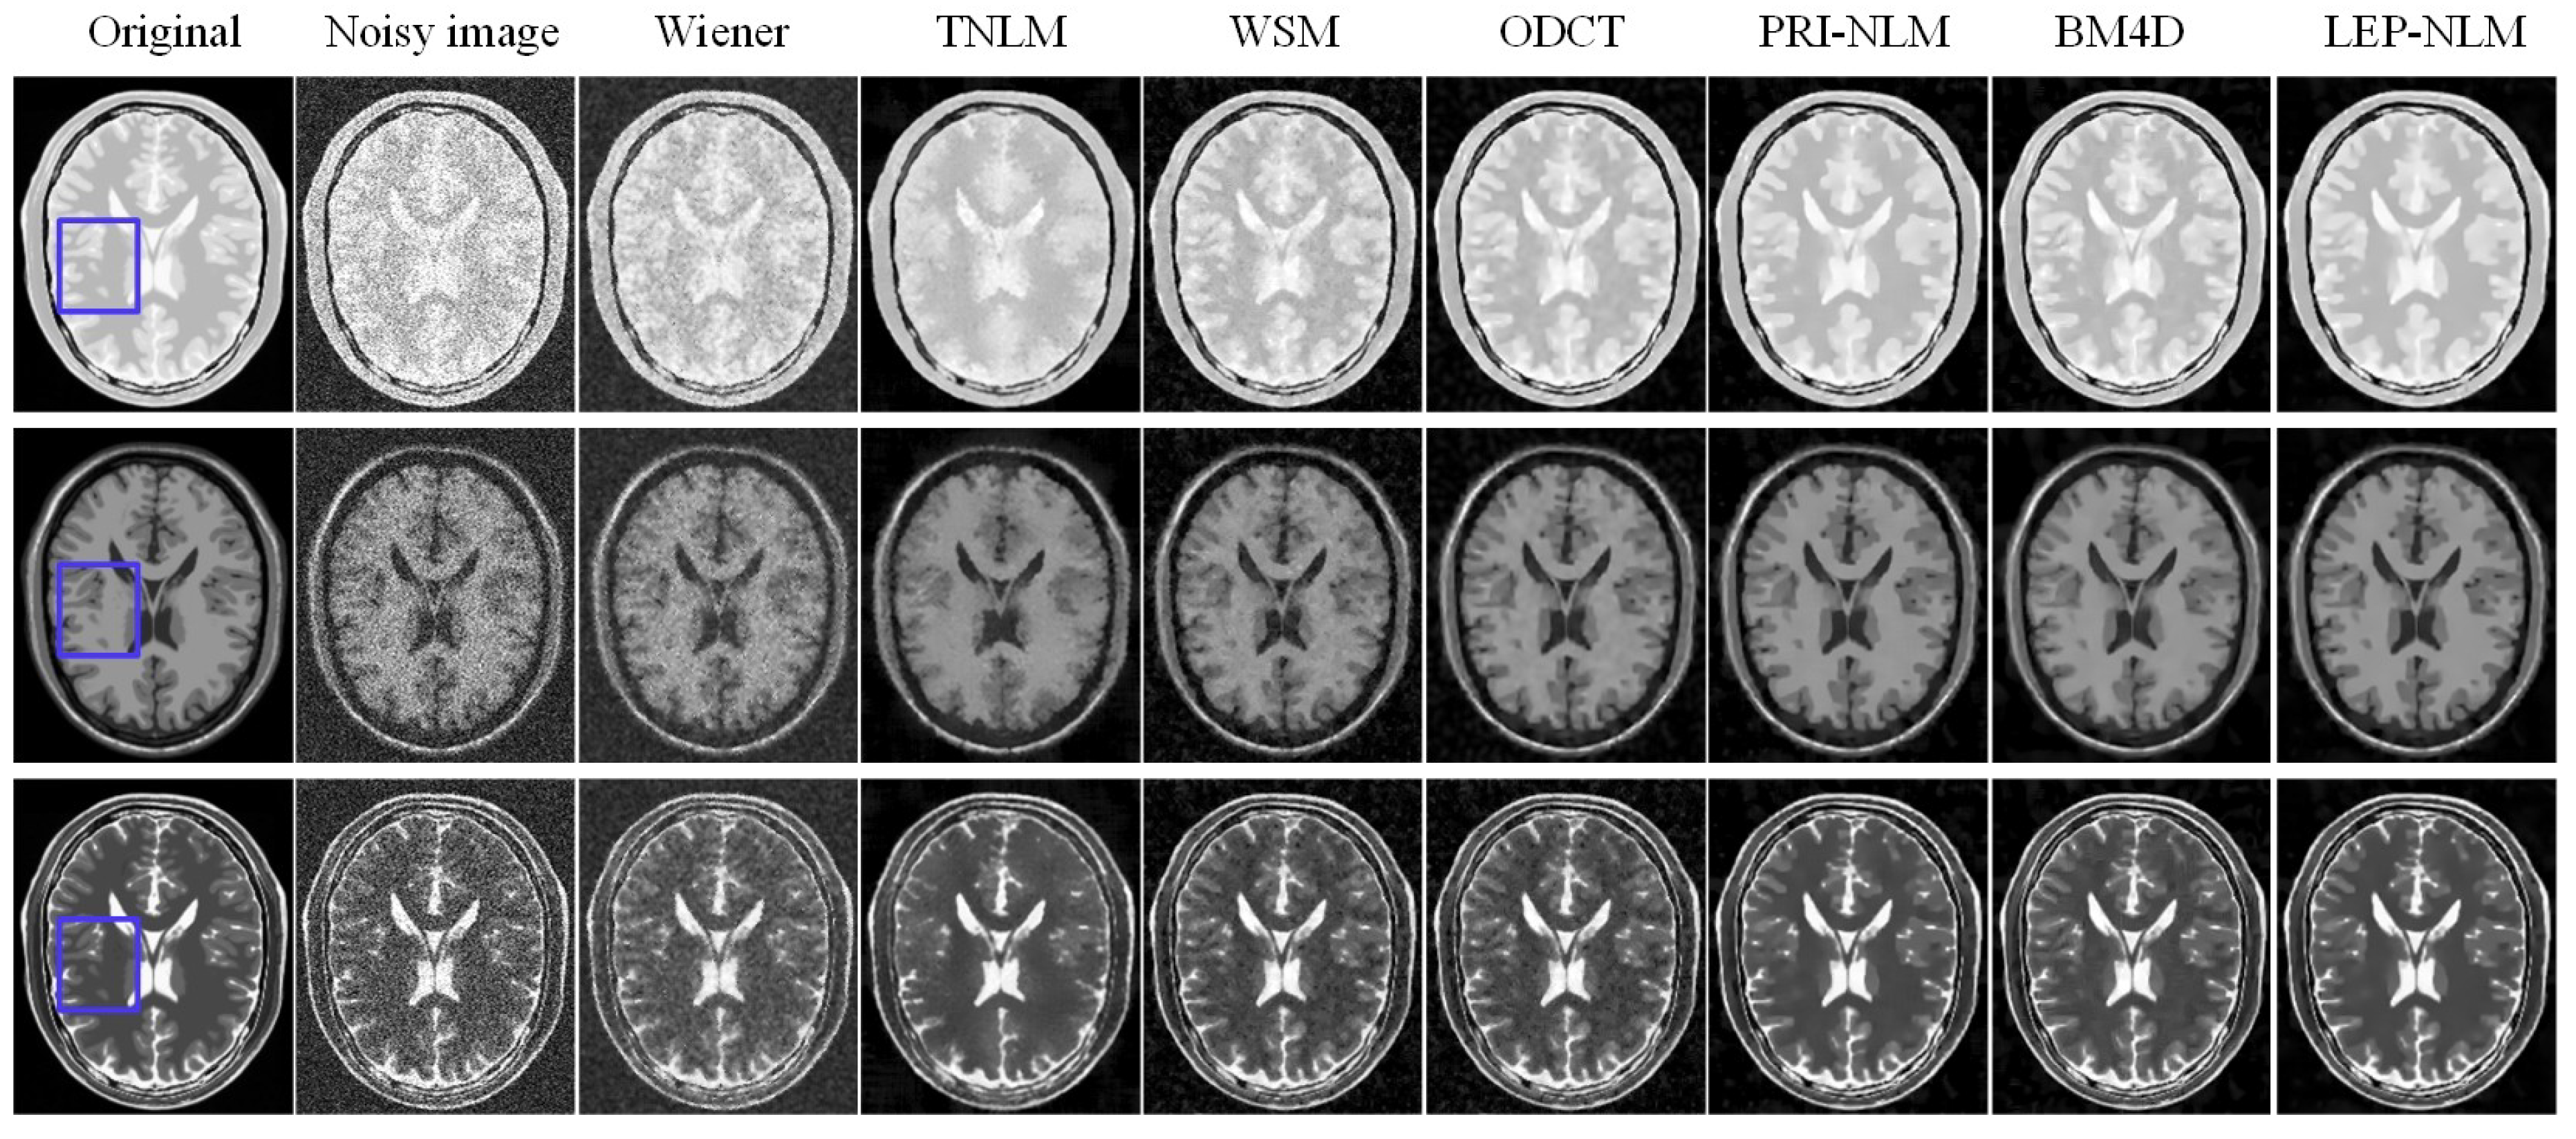

3.1. Simulated MR Images